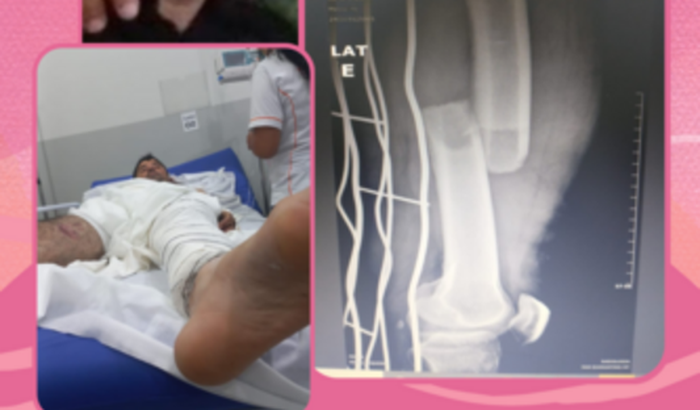

Ajuda em prol do Jeremias que sofreu um acidente e quebrou o fêmur precisamos de ajuda para sua recuperação

vamos ajudar o Jeremias um homem trabalhador que estava trabalhando no momento que sofreu um acidente e quebrou a perna fêmur e irá ficar alguns meses sem poder trabalhar até se recuperar vamos ajudar na sua recuperação  ver tudo

vamos ajudar o Jeremias um homem trabalhador que estava trabalhando no momento que sofreu um acidente e quebrou a perna fêmur e irá ficar alguns meses sem poder trabalhar até se recuperar vamos ajudar na sua recuperação